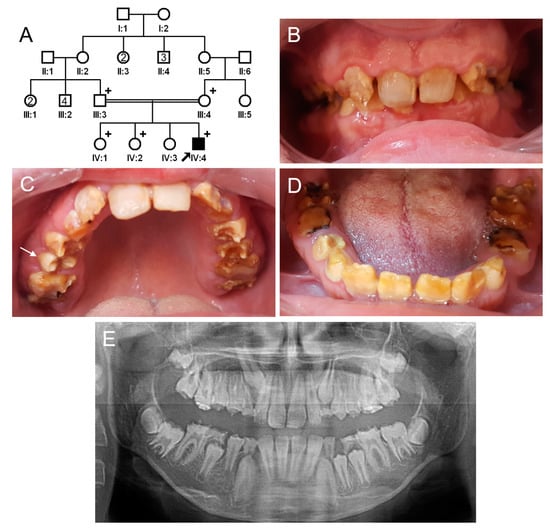

3.4. Family 4

The proband of family 4 was a 10-year-old female from a consanguineous Turkish family (Figure 7). She had no remarkable past medical history. Her deciduous and permanent dentition had a dark brown discoloration and exhibited enamel breakdown and accelerated attritions. There were black stains throughout the dentition. She had no kidney symptoms, and the pediatric nephrology department confirmed that she had no acidosis, and her renal and tubule functions were normal. She was the only affected individual in her family; therefore, a recessive or de novo mutation was suspected.

Figure 7.

Pedigree, clinical photos, and panoramic radiograph of family 4. (A) Pedigree of family 4. The black symbol indicates the affected individual, and the proband is indicated by a black arrow. A plus sign above the symbol indicates participating individuals. The number inside the symbol indicates the number of siblings with the same gender. (B–D) Clinical photos of the proband at age 10 years. Permanent and deciduous dentitions show dark brown discoloration and exhibit enamel fractures and accelerated attrition. Black external stain is observed on most teeth. (E) A panoramic radiograph of the proband at age 10 years shows irregular crown surfaces and enamel with reduced radiopacity and fractures. However, the developing crowns are normal in shape.